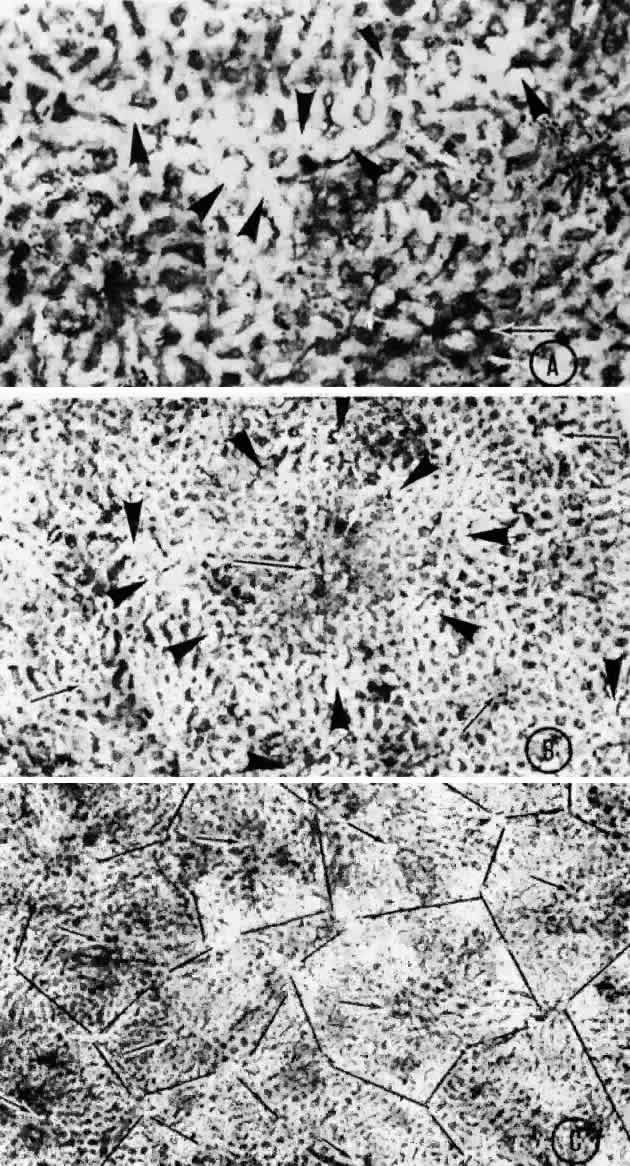

histologic sections (Figs. 21, 22, and 23). They described the overall appearance of the posterior choriocapillaris

as a series of adjoining lobules that was striking in some preparations

and subtle in others. The center of the lobule consisted of a single

precapillary arteriole rimmed in a thick mantle of collagen measuring 15 to 25 μm

and opening perpendicularly or curvilinearly into

a capillary bed that radiated an average distance of 300 to 400 μm

before changing from a radial to a circumferential direction. The circumferential

capillaries in the periphery of the lobule were wider and

converged from several directions, forming star-like or dendritiform configurations

in the plane of the choriocapillaris. Venular openings, outward

bulgings of the external choriocapillaris called atria, measured 30 to 37.5 μm and were present singly and in linear sequences

underlying the circumferential capillaries. The often incomplete lobules

varied in their geometric configuration, having three to six sides

and ranging in area from 420 × 605 μm to 800 × 1200 μm. The

lobular unit was thought to provide a preferred outflow route

via the perimeter of postcapillary venules so that cross-flow from

lobule to lobule would not normally occur, and thus the precapillary

arteriole would function as an end-arteriole.  Fig. 21. Flat preparation of choriocapillaris, posterior pole. A. Arrowheads indicate oval openings to the postcapillary venules. The area

arteriole would function as an end-arteriole.  Fig. 21. Flat preparation of choriocapillaris, posterior pole. A. Arrowheads indicate oval openings to the postcapillary venules. The area

around the precapillary arteriole (white-bordered arrow) is stained more heavily because of residual subcapillary collagen. (PAS, × 180; AFIP

Neg 74-9984) B. Postcapillary venules (arrowheads) form an irregular ring bordering the capillaries that radiate from the

precapillary arteriole (white-bordered arrows), thus outlining a single lobule. The capillaries are broader and clearer

near the venules because of less subcapillary collagen. (PAS, × 100, AFIP

Neg 74-10240) C. The openings of the postcapillary venules (as shown above) are connected

with black lines; they demarcate adjoining lobules in the choriocapillaris. Capillaries

from adjoining lobules enter the intervening venules. The

lobules form a mosaic of adjoining vascular beds. Precapillary

arterioles are indicated by white-bordered arrows. (PAS × 55; AFIP

Neg 74-9985) Fig. 21. Flat preparation of choriocapillaris, posterior pole. A. Arrowheads indicate oval openings to the postcapillary venules. The area

Fig. 22. Choriocapillaris in periphery has long, thin intercapillary septa. Arteriole

in capillary plane (curved arrow). Venous anastomosis (arrowheads). (AFIP Neg 73-11415 and 12110; PAS, × 50) Fig. 22. Choriocapillaris in periphery has long, thin intercapillary septa. Arteriole

in capillary plane (curved arrow). Venous anastomosis (arrowheads). (AFIP Neg 73-11415 and 12110; PAS, × 50)

Fig. 23. Prominent lobular pattern in choriocapillaris with venules (arrowheads) surrounding arterioles (arrows). (AFIP Neg 75-3895; PAS, × 55) (Torczynski E, Tso M: The architecture of the choriocapillaris at the posterior

pole. Am J Ophthalmol 81:428, 1976) Fig. 23. Prominent lobular pattern in choriocapillaris with venules (arrowheads) surrounding arterioles (arrows). (AFIP Neg 75-3895; PAS, × 55) (Torczynski E, Tso M: The architecture of the choriocapillaris at the posterior

pole. Am J Ophthalmol 81:428, 1976)